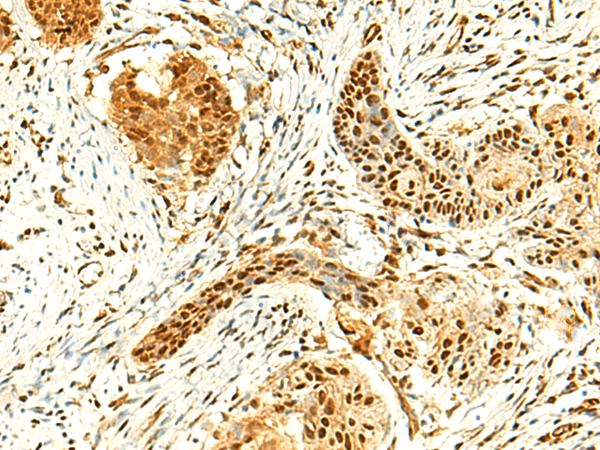

分类: 科研抗体货号: P10112别名: PUS4应用: IHC反应种属: Human, Mouse, Rat